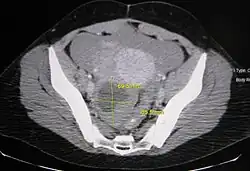

Transvaginal ultrasonography showing a 67 x 40 mm endometrioma, with a somewhat grainy content.

Ovarian cysts are considered large when they are over 5 cm and giant when they are over 15 cm. In children, ovarian cysts reaching above the level of the umbilicus are considered giant.